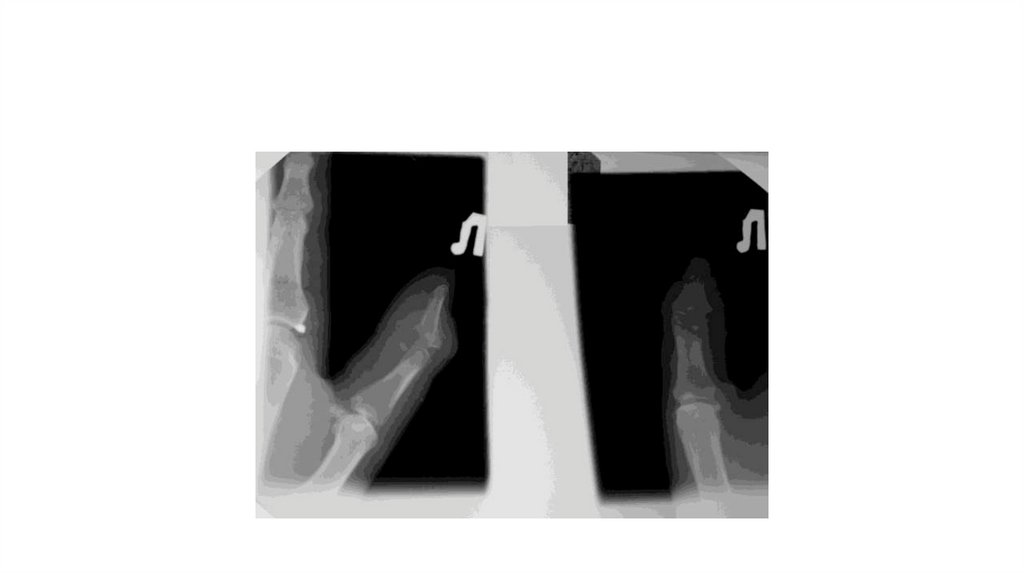

Воспалительные заболевания опорнодвигательного аппарата

«Воспалительные

заболевания опорнодвигательного аппарата»